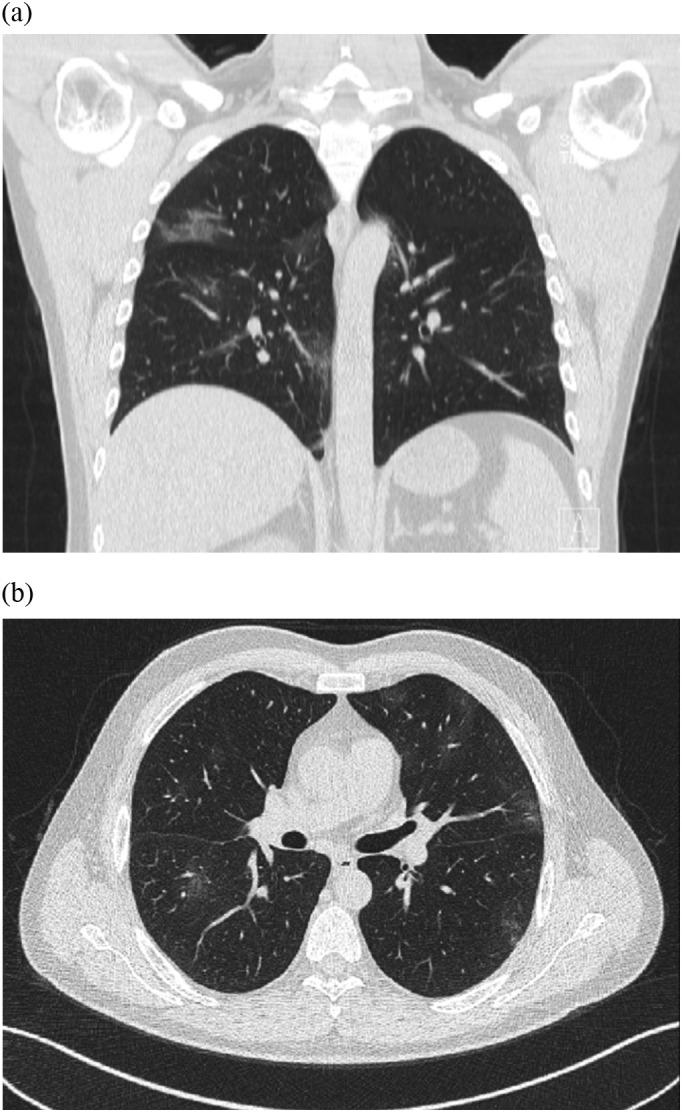

Transient cortical blindness in COVID-19 pneumonia; a PRES-like syndrome: Case report.

J Neurol Sci. 2020 Jun 15;413:116858. doi: 10.1016/j.jns.2020.116858. Epub 2020 Apr 28.